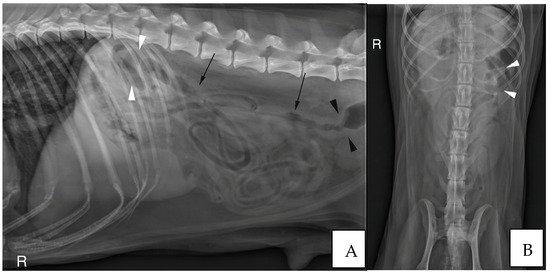

3.2.3. Abdominal Radiographs

| Severity of Colonic Wall Thickening | Unremarkable | Mild | Moderate | Severe |

|---|---|---|---|---|

| Group A (/11 cases) | 3 | 3 | 4 | 1 |

| Group B (/8 cases) | 3 | 2 | 2 | 1 |